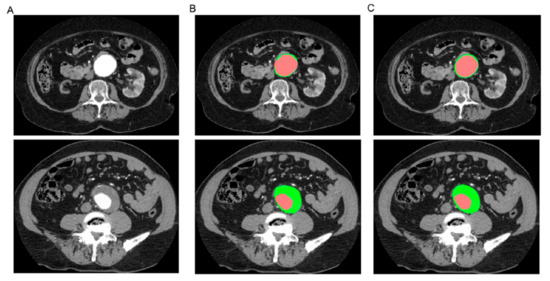

- Lareyre, F.; Adam, C.; Carrier, M.; Dommerc, C.; Mialhe, C.; Raffort, J. A fully automated pipeline for mining abdominal aortic aneurysm using image segmentation. Sci. Rep. 2019, 9, 13750. [Google Scholar] [CrossRef] [PubMed]

- Spinella, G.; Fantazzini, A.; Finotello, A.; Vincenzi, E.; Boschetti, G.A.; Brutti, F.; Magliocco, M.; Pane, B.; Basso, C.; Conti, M. Artificial Intelligence Application to Screen Abdominal Aortic Aneurysm Using Computed tomography Angiography. J. Digit. Imaging 2023, 36, 2125–2137. [Google Scholar] [CrossRef] [PubMed]